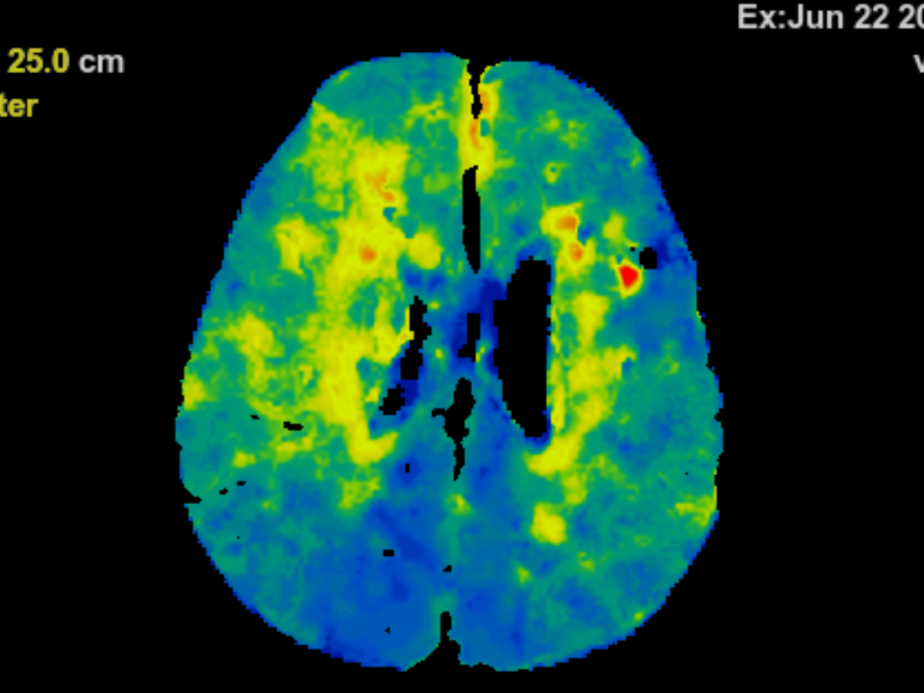

此外,通过经进一步检查,蔡利发现龚小姐的双侧颈内动脉存在严重的闭塞和脑底毛细血管增生,其中颈内动脉的供血量占脑部血液的80%,不解决闭塞状况其症状很可能会再次发作。“从脑血流灌注成像图可以看出,她的大脑血液灌注量低,迫切需要获得足够血液。”蔡利说。

术后脑血流灌注成像图显示,黄色和红色区域基本消失,大脑供血恢复明显

2小时后,新的供血通路成功建立。术后脑血流灌注成像图显示,此前的缺血区域供血基本恢复了正常。患者也表示,眼睛看东西清晰了很多,表明手术疗效初步显现。